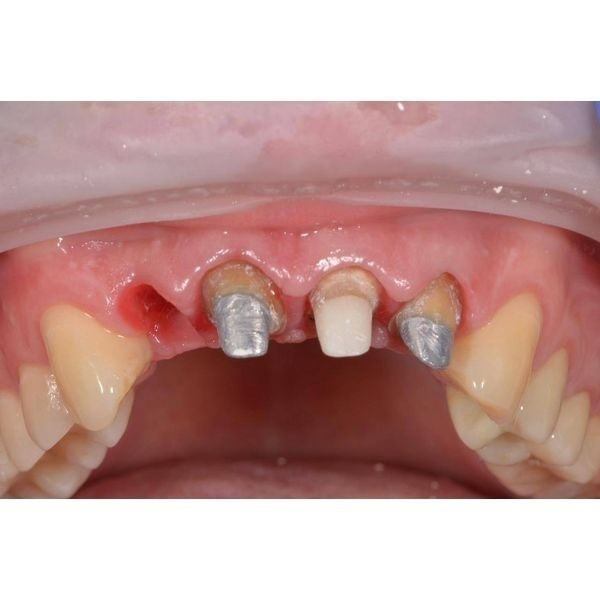

На 5-м посещении мужчине удалили зуб 1.2 и одномоментно провели имплантацию системой Astra-tech TX. В тот же день ему поставили имплантаты на место отсутствующих зубов, а также установили формирователи десны.

Через 10 дней после имплантации пациенту сняли швы и провели временное протезирование.